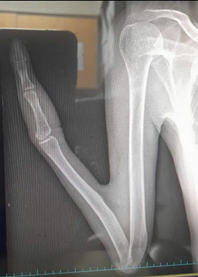

A 57-year-old healthy male with a right medial malleolus fracture was referred to the Orthopedic Center of Boo-Ali Sina Hospital in Sari, Mazandaran, Northern Iran. A congenital anomaly in the patient's right upper extremity was detected during a physical examination. In comparison to the unaffected limb, the affected limb exhibited significant shortening, pronation, and internal rotation. Notably, the shoulder joint remained unaffected. Subsequent radiographic examinations revealed the presence of radiohumeral synostosis, complete absence of the carpal and ulna bones, and a bowed and shortened radius. Furthermore, the hand exhibited only the thumb and the first metacarpal bone, with the wrist showing a distinctive curvature in the direction of the ulna. The elbow's range of motion was limited due to congenital webbing (pterygium), and the fingers displayed restricted mobility. (Figure 1 & 2) Comprehensive assessments of the musculoskeletal system revealed no additional issues, and there were no indications of other organs being affected.

Figure 2A radiograph of the right upper limb illustrating the absence of the ulna and monodactyly.